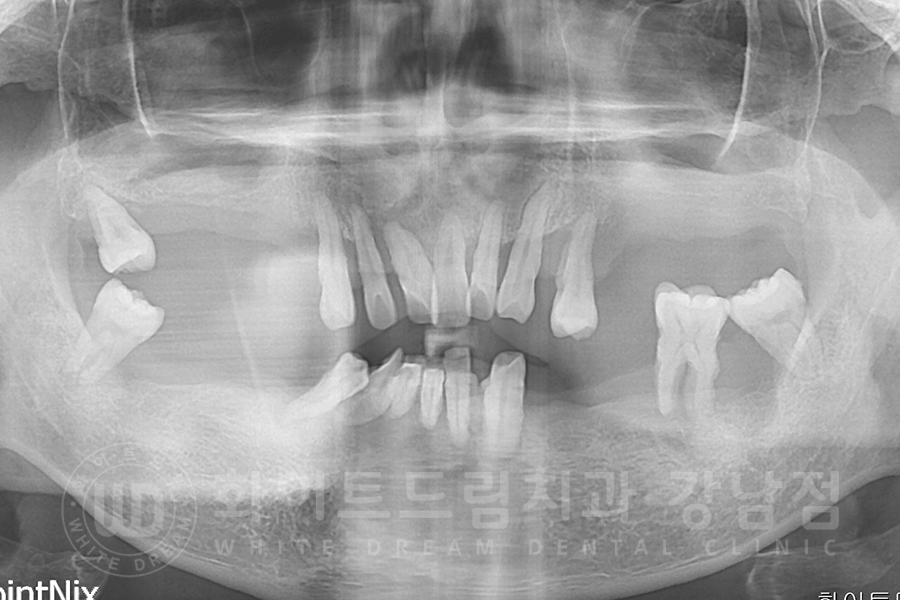

환자분의 x-ray를 보면 대다수의 치아가 없는 상태이고,

그나마 남아있는 치아들도 쓰러져있거나 치아 뿌리만 잇몸뼈에 겨우 매달려있는 상태였습니다.

치주염이 굉장히 심한 상태여서 살릴 수 있는 치아는 없었기에

전악 발치 후 전체 임플란트 치료를 진행하기로 했습니다.